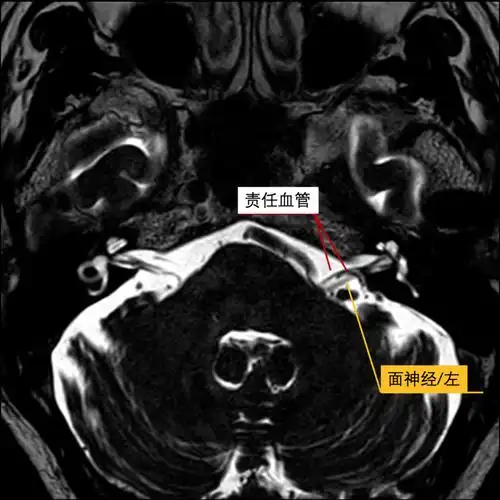

该病典型的 mri 表现为双侧面神经发育不全,在平衡稳态梯度回波序列

面神经解剖及相关病变